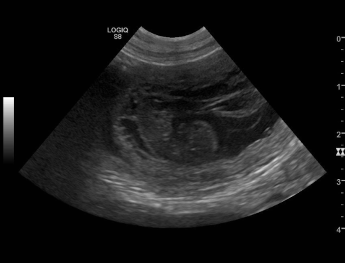

Sookie und Uaine erwarten Babies! Die Ultraschallbilder beweisen es! Hier sind die Bilder!!! |

| Die Ultraschallbilder von Uaine von Waltenweiler!!! |